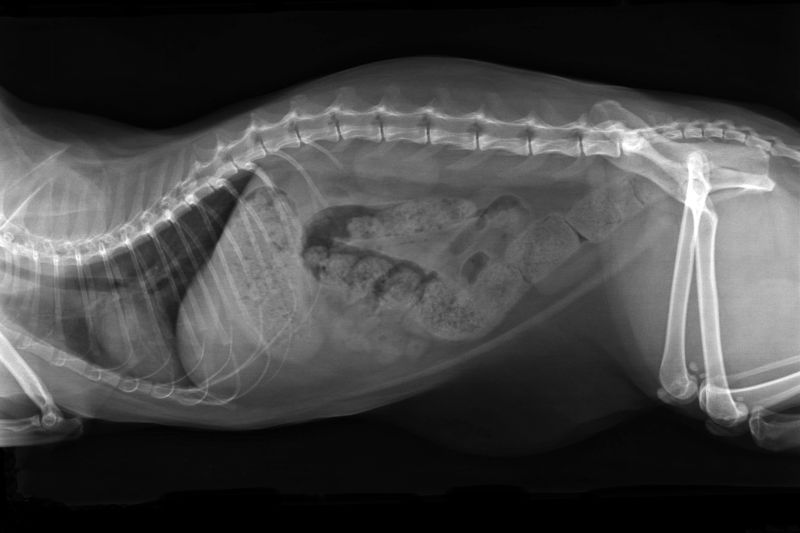

Diagnosis will usually include a medical history, physical examination and microscopic faecal evaluation. It is important to take a fresh stool sample to your consultation; it will help the vet identify potential underlying causes for the abnormal faeces. The stool sample will be examined for blood, parasites and bacteria. In more serious cases, x-rays, ultrasound, and blood and urine tests may also be conducted.

Diagnostic imaging

X-rays may be recommended if a tumour, foreign body, or anatomical problem is suspected. A barium study or ultrasound may also be recommended. Examinations using an endoscope or colonoscopy may be performed in certain cases.